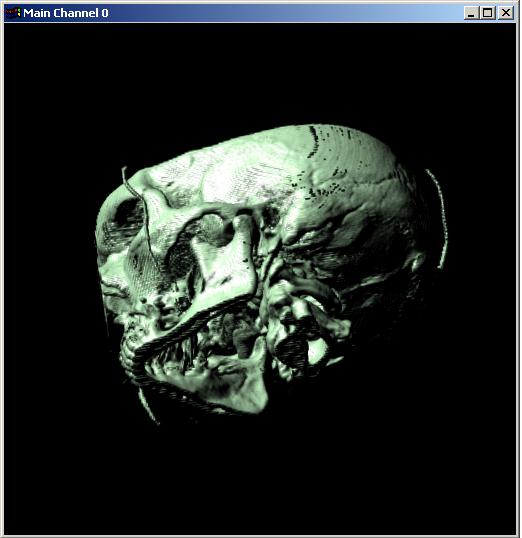

Visible human male CT data

Data

Resolution : 256x256x128

The following 12

images was generated by PC which has NVIDIA's GeForce3 GPU graphics card. The

hardware accelerated rendering techniques are used to make the following images.

To use the GeForce3 hardware, we have to use the OpenGL extensions like

GL_NV_texture_shader2, GL_NV_register_combiners, GL_EXT_texture3D,

GL_EXT_paletted_texture, GL_ARB_multitexture and so on. Since the GeForce3 card

allows the 3D texture shading, the image quality is better than the pixel of

frame buffer based shading in showing two materials at the same time.